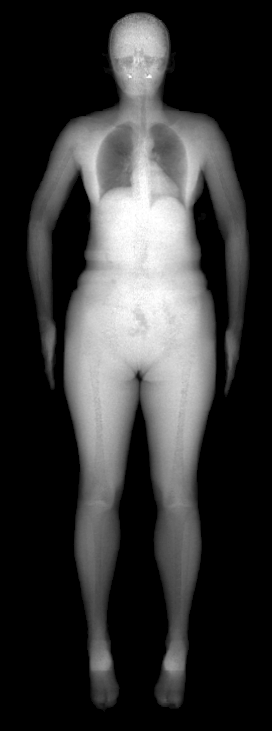

The key problem, however, is obtaining training data that simultaneously gives the inside and outside of the body in 3D. Most imaging technologies that simultaneously capture the inside and outside of the body use ionizing radiation, which is harmful to humans; e.g. Computed Tomography (CT) and X-rays. This means that such data is extremely limited, preventing learning-based methods. Our insight is to use dual-energy X-ray absorptiometry (DXA) data. DXA scans use low-dose X-rays to measure bone mineral density and body fat composition. The radiation level is so low that it is certified to be used on healthy patients for clinical studies, such as the UK Biobank [36]. In a DXA scan, two images are computed by combining two different energy levels: a soft-tissue image and a bone image (Fig. 2). In the silhouette of the body can clearly be seen, whereas reveals the structure and shape of the bones.

From the input images (, ), we compute the corresponding skin and skeleton segmentation masks (, ). For the skin mask , we threshold . As some small artifacts remain, mainly due to pixels in the lungs with low intensity values, we detect the closed contours on the image and fill in small areas. In Fig. 2 we show pairs of input and the obtained mask .